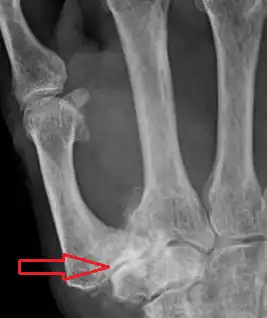

Description de l'image Osteoarthritis of the CMC joint.png.

Signes radiographiques

La rhizarthrose se présente sur une radiographie avec des signes classiques d'arthrose : diminution de l'interligne articulaire, ostéophytes (bec de perroquet) marginaux, condensation osseuse sous le cartilage, géode d'hyperpression puis usure osseuse. À ces signes habituels qui définissent l'arthrose vont s'associer dans la majorité des cas une subluxation de la base du premier métacarpien en externe. L'arthrose peut être limitée à l'interligne entre l'os trapèze et le métacarpien ou s'étendre à l'interligne articulaire avec l'os scaphoïde, scapho-trapézo-trapézoïdien (STT), on parle alors dans ce cas d'arthrose péri-trapézienne[4].